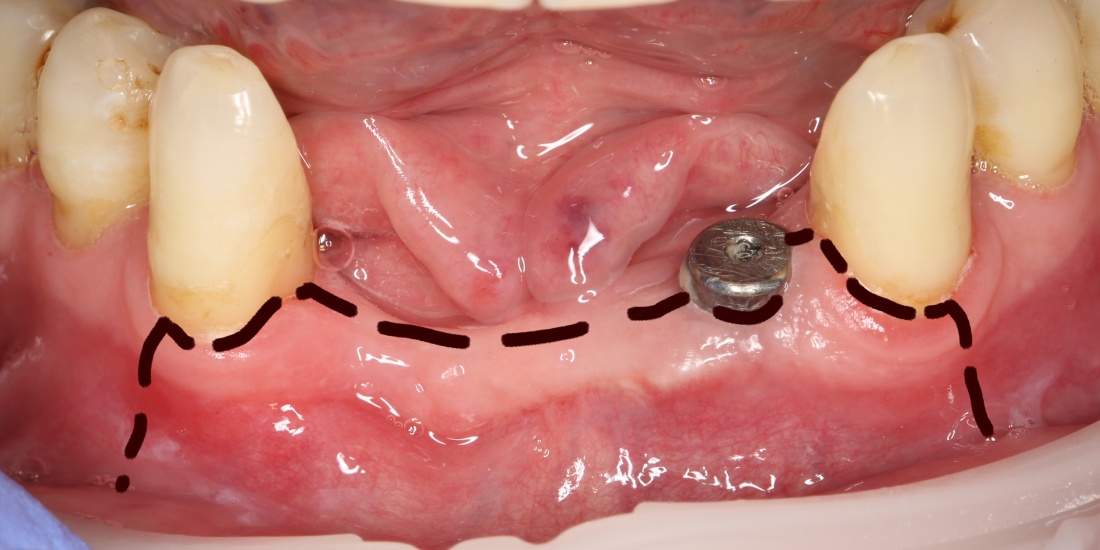

Что происходит дальше, известно достаточно хорошо. Образовавшаяся периимплантитная «воронка» открывает поверхность имплантата для доступа ротовой жидкости и микрофлоры.

Ротовая жидкость образует упоминавшуюся С. Ренвертом «биоплёнку» из гликопротеинов на поверхности имплантата, последняя становится приютом для микроорганизмов — к изначально асептическому («чистому») остеолизу присоединяется инфекция со всеми вытекающими. Развивается инфекционно-воспалительный процесс, затрагиваемый, преимущественно, слизистую оболочку — т. н. «мукозит».

За фото не переживайте — эту пациентку мы вылечили))))

То есть, инфекция, какой бы она ни была, не является первопричиной периимплантита, но её присоединение существенно усугубляет процесс и добавляет разнообразия симптоматике — именно с этого момента пациент начинает чувствовать неприятный запах, дискомфорт в области установленного имплантата, периодически возникающее воспаление десны, выделения из десневого кармана и т. д. Проведённое протезирование создаёт достаточное пространство для ретенции зубного налёта и в некоторых случаях существенно осложняет гигиену в области шеек имплантатов — развитие периимплантита, уже не просто воспалительного, а инфекционно-воспалительного процесса ускоряется и усугубляется (мы же не просто так просим делать профессиональную гигиену и пользоваться ирригатором все пациентов с имплантатами).